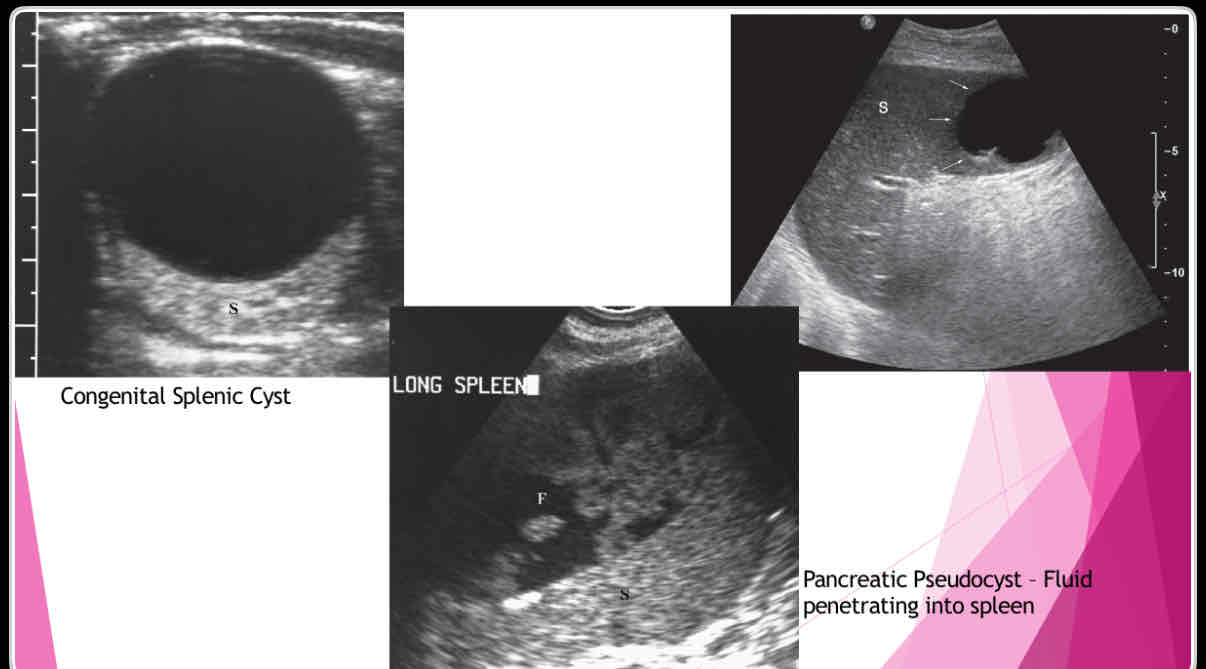

What does the following describe?

•Anechoic, well-defined walls, enhanced sound transmission

•Sharply demarcated wall, multilocular internal structure representing daughter cyst, mural calcifications

•Large cysts, dense, clearly defined walls May not have well-defined wall, mural calcifications Single or multiple simple cysts

splenic cysts

What are the different types of splenic cysts?

•Can be Congenital

•Can also be Acquired

• Echinococcal (hydatid)

•Epidermoid or epithelial

•Posttraumatic or postinflammatory pseudocysts

What does the following describe?

•True cysts lined by squamous epithelium

•Typically solitary, 10 cm

•Wall may be calcified and internal contents echogenic

Epidermoid or epithelial

What does the following describe?

•Polycystic kidney disease lymphangioma,

•extension of pancreatic pseudocyst

-Erode into spleen due to proximity

-May weaken vessels causing pseudoaneurysms and bleeding into pseudocyst

Posttraumatic or postinflammatory pseudocysts